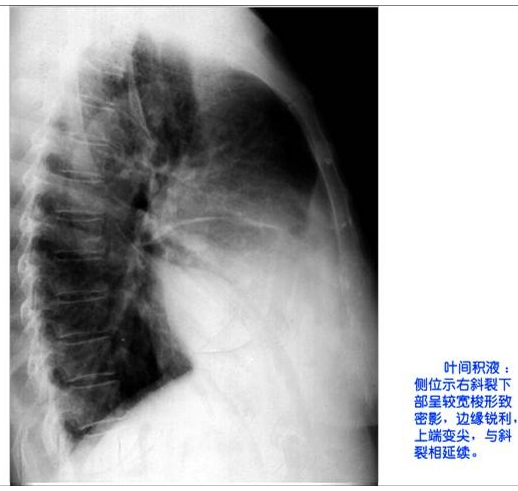

照片名称:叶间积液